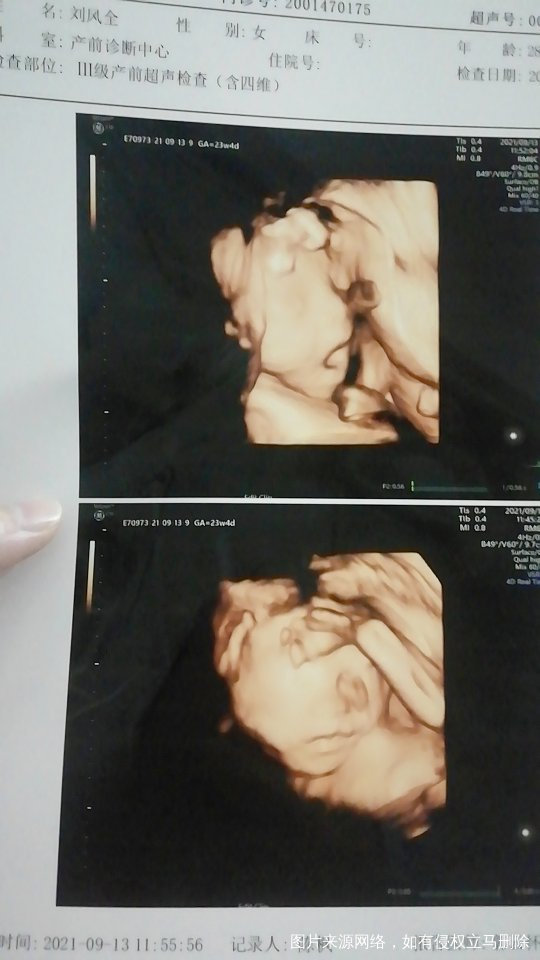

医师 你好 我现在怀孕6个月了 这两天什么都没做 也没有哪里不舒服 就突然的流黑褐色分泌物 下面大小阴唇有点变大 像是有点肿 之前5个月的时候 也出现一次比较多的黑色分泌物 这是怎么回事 什么原因呢